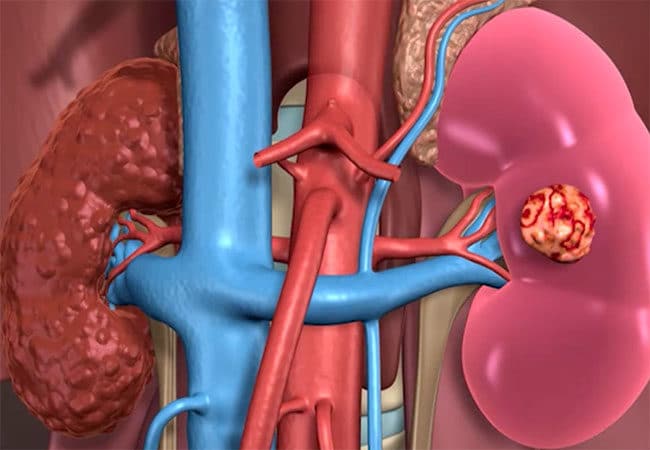

;Η νεφρική νόσος που προκαλείται από τον σακχαρώδη διαβήτη και την υπέρταση παίρνει πλέον διαστάσεις επιδημίας. Η παχυσαρκία και η νεφρική νόσος που σχετίζεται με τον τρόπο ζωής είναι επίσης σε άνοδο. «Λοιμώξεις των νεφρών και του ουροποιητικού συστήματος, πέτρες στα νεφρά, ουσία και φάρμακα α